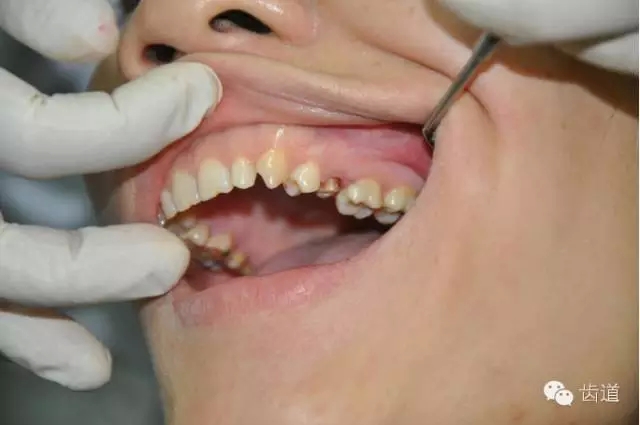

在口腔修復(fù)中,對于需要做全冠的牙齒要進(jìn)行牙體預(yù)備,靠近牙齦的地方所均勻磨出的一圈平臺稱肩臺。

如果肩臺制備不到位或不制備肩臺,全冠戴入后冠邊緣就會形成異物懸突,刺激牙齦,引起齦發(fā)炎出血,時間一長甚至?xí)?dǎo)致牙冠腐爛。

1.修復(fù)體邊緣密合性檢查困難。(如果修復(fù)體邊緣形成懸突,不密或 不光滑,容易對牙齦產(chǎn)生機(jī)械性和細(xì)菌性刺激)

2.如果印模齦緣處不清晰,技工將很難掌握肩臺的位置,最終修復(fù)將有可能出現(xiàn)內(nèi)冠邊緣懸突和肩臺懸突的問題。

內(nèi)冠邊緣懸突是導(dǎo)致牙齦變色的"罪魁禍?zhǔn)?quot;

肩臺懸突易出現(xiàn)繼發(fā)齲